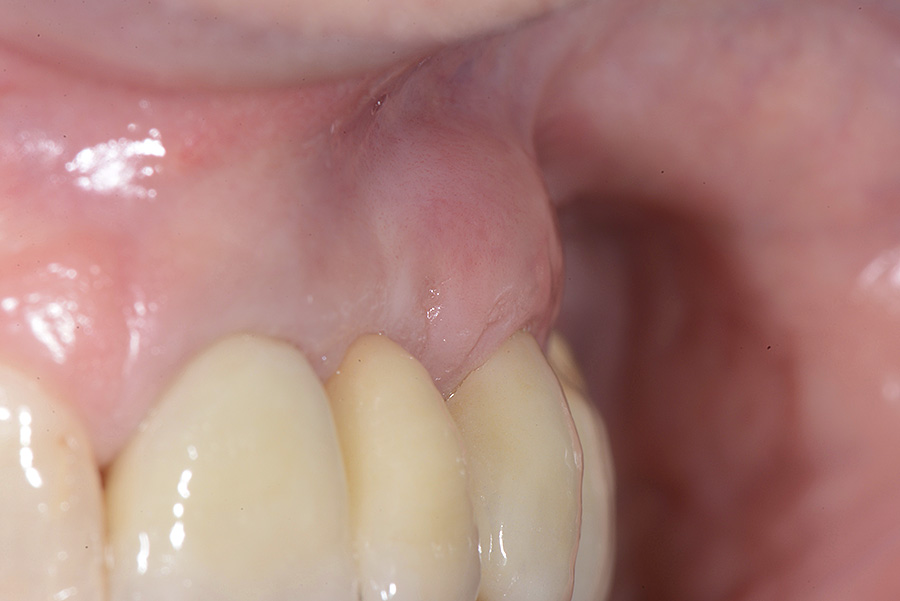

PREMESSA: in seguito all’estrazione dell’incisivo laterale superiore di destra, resasi necessaria per cause batteriche, si decide di affrontare il caso con il posizionamento di un impianto in sostituzione dell’elemento mancante dopo guarigione del sito infetto. Con tecniche rigenerative sia dei tessuti ossei mancanti a causa dell’infezione pregressa, sia dei tessuti gengivali che appaiono inizialmente troppo spostati in alto, si ripristina una corretta morfologia delle parabole (contorni) gengivali e delle papille interdentali (triangoli di gengiva tra due denti vicini).